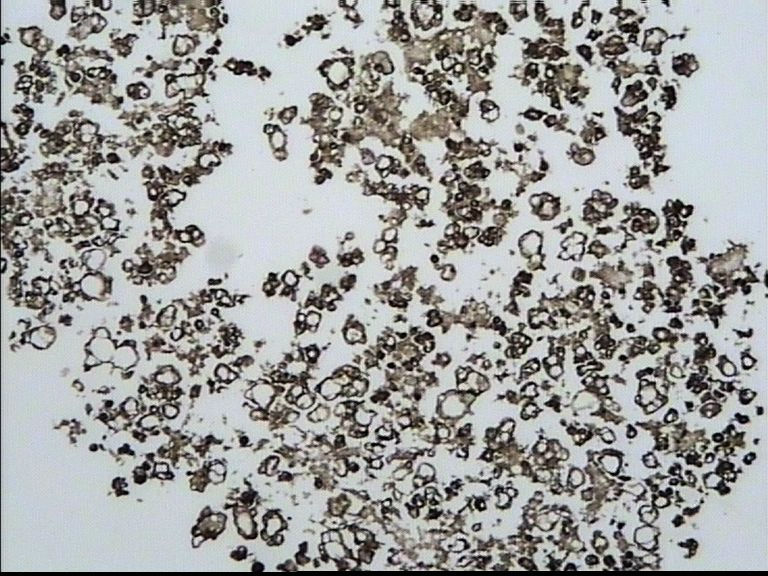

67岁 男 胸水组织块

• 67岁 男 胸水组织块图1

图1

TTF-1

ck7

CEA

肺腺癌细胞

肺腺癌